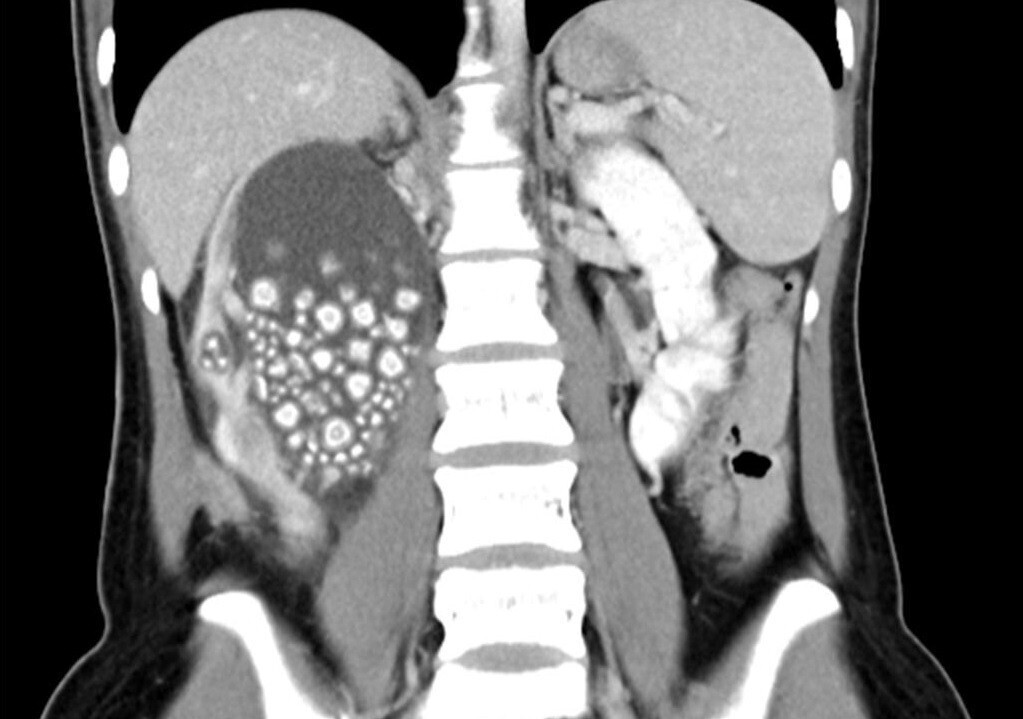

엑스레이를 통해 그녀의 신장은 수백 개의 작은 신장 결석으로 부풀어 있었습니다.

결석사진나와유